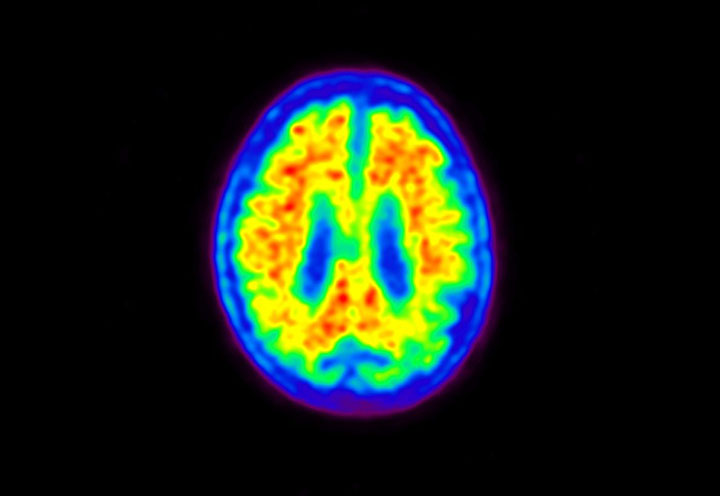

Head / Case5 : Amyloid

Courtesy : Kindai University Hospital

- Imaging protocol

- Injected dose: 4.27 MBq/kg, 18F-Flutemetamol

- Uptake time: 99 minutes

- Scan time: 20 minutes